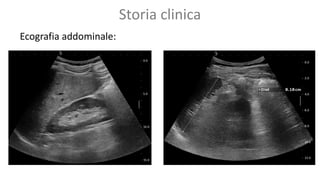

Storia clinica

Ecografia addominale: